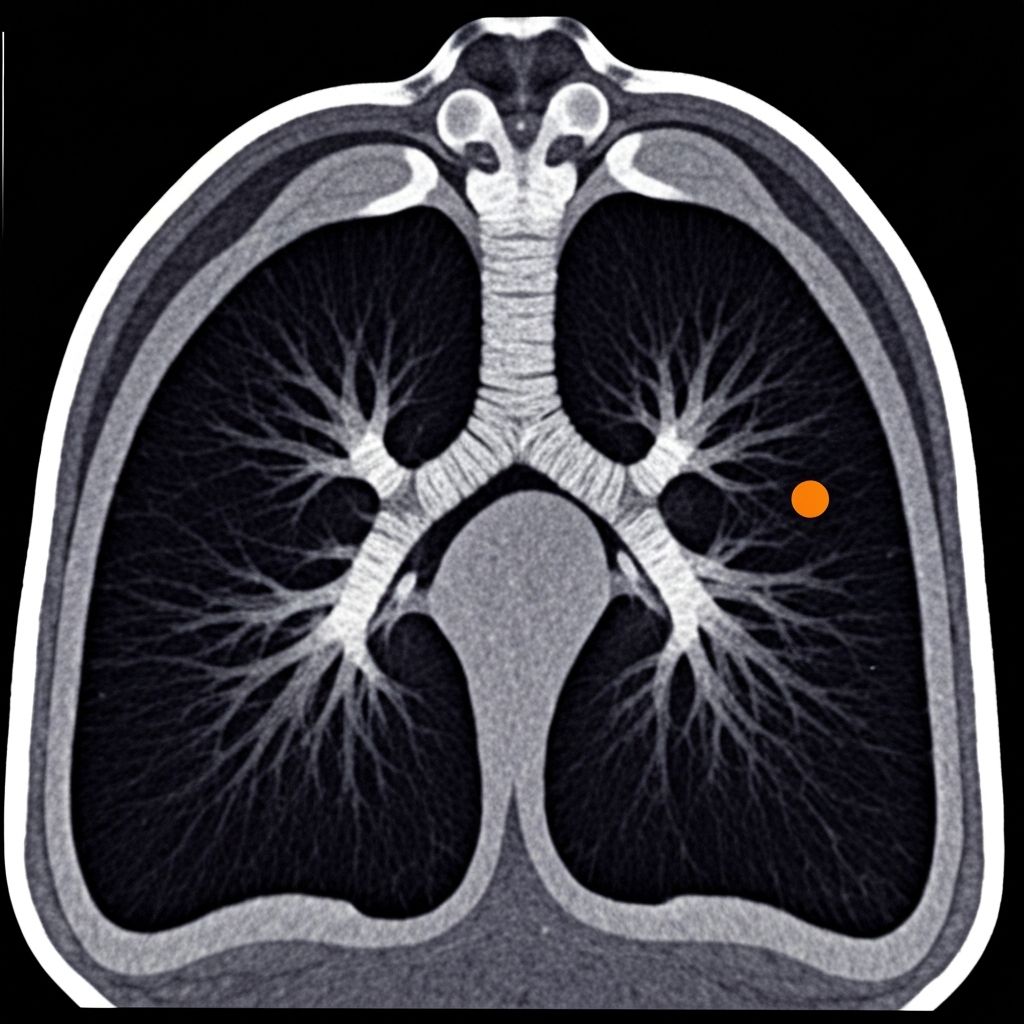

CT CHEST 2025

COMPARISON VIEW

SLICE 47/128